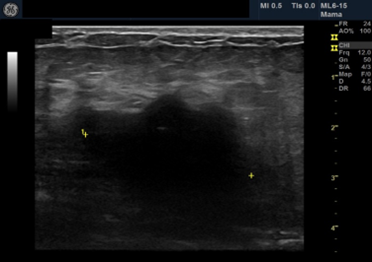

Female patient, black, 76 years old, G3P3, complaining of a lump in the right breast that had appeared 8 months ago. He has a history of admission to the intensive care unit 10 months ago due to an ischemic stroke, presenting left hemiparesis. Presents hypertension, hypothyroidism and dyslipidemia. Family history of father with prostate cancer. He presents sclerocalcification in the mitral and aortic valve on the echocardiogram. He presented clinical signs of an initial dementia process.Ultrasonography showed a heterogeneous image of 3.9/2.4/3.7cm in the union of the upper quadrants of the right breast, axillary lymph nodes with proportionality between cortex and hilum bilaterally BI-RADS 4 B BI-RADS 4 B.

On palpation, there was an 8cm nodule in the right breast and mobile and fibroelastic axillary lymph nodes. There were no palpable nodules in the cervical or supraclavicular region bilaterally. A core needle biopsy was performed with an anatomopathological result of triple-negative grade 2 adenoid cystic carcinoma. Staging demonstrated two 1.1cm pulmonary nodules with soft tissue density suggesting metastasis. Abdominal tomography demonstrated liver nodules suggestive of secondary implants. The PET scan confirmed uptake in the lung and liver nodules, in addition to lytic lesions in S3. Liver biopsy confirmed implantation of adenoid cystic carcinoma. The patient was staged as T2N0M1. Chemotherapy was started with a regimen of Carboplatin, Paclitaxel and Pembrolizumab. After the third cycle of chemotherapy, the breast was reevaluated without showing any tumor reduction. The metastases also did not regress, and treatment was interrupted. The patient evaded the service until he returned in January 2024 complaining of pain in his right hip and difficulty walking. Chest and hip tomography showed an increase in lung lesions and the appearance of lytic metastasis in the iliac bone (figure 1, 2, 3).

Figure 2: